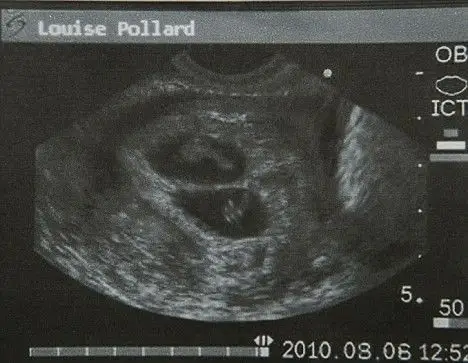

b超显示路易斯怀上了双胞胎